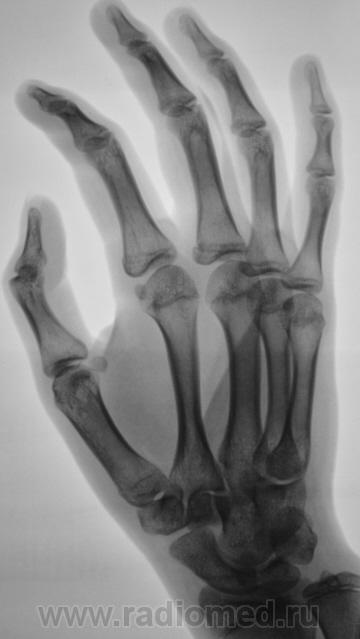

Пациентка направлена хирургом в рентгеновский кабинет для рентгенографии кисти и лучезапястного сустава. Вроде-бы, была и травма, после которой появилась боль в лучезапястном суставе.

перелом крючковидной кости, м.б и гороховидной (по поводу последней не очень уверен)

Укладки на трехгранную кость, она смещена каудально и радиально, структура неоднородная, но на счет перелома не уверена, а вот вывих трёхгранной кости есть.

Смущает перестройка структуры костной ткани, помечено стрелками.

Похоже на кисты (здесь - врождённые)

А может ГКО?